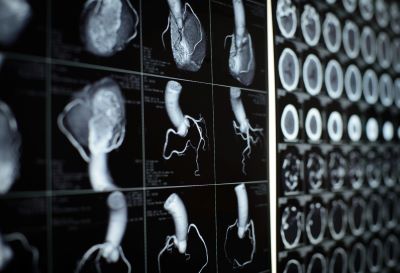

El término "tomografía computarizada", o TC, se refiere a un procedimiento computarizado de toma de imágenes con rayos X en el que se proyecta un haz angosto de rayos X a un paciente y se gira rápidamente alrededor del cuerpo, produciendo señales que son procesadas por la computadora de la máquina para generar imágenes transversales, o "cortes". Estos cortes se llaman imágenes tomográficas y pueden brindar al médico información más detallada que las radiografías convencionales. Una vez que la computadora de la máquina recopila varios cortes sucesivos, estos se pueden "apilar" digitalmente para formar una imagen tridimensional del paciente que permite identificar más fácilmente las estructuras básicas, así como posibles tumores o anomalías.

La computadora puede mostrar los cortes de imágenes en forma individual o apiladas, para generar una imagen 3D del paciente que muestre el esqueleto, los órganos y los tejidos, así como cualquier anomalía que el médico esté tratando de identificar. Este método tiene muchas ventajas, incluyendo la capacidad de rotar la imagen 3D en el espacio o ver cortes en sucesión, lo que facilita encontrar el lugar exacto donde se puede ubicar un problema.

Las tomografías computarizadas se pueden usar para identificar enfermedades o lesiones en varias regiones del cuerpo. Por ejemplo, la TC se ha convertido en una herramienta útil para detectar posibles tumores o lesiones dentro del abdomen. Una TC del corazón puede ser recetada cuando se sospechan varios tipos de enfermedades o anomalías cardíacas. La TC se puede utilizar también para obtener imágenes de la cabeza a fin de localizar lesiones, tumores, coágulos que puedan provocar un derrame cerebral, hemorragia y otras afecciones. Puede tomar imágenes de los pulmones para revelar la presencia de tumores, embolias pulmonares (coágulos de sangre), exceso de líquido y otras afecciones, como enfisema o neumonía. Una TC es particularmente útil para obtener imágenes de fracturas óseas complejas, articulaciones severamente erosionadas o tumores óseos, ya que generalmente produce más detalle del que se podría obtener con una radiografía convencional.